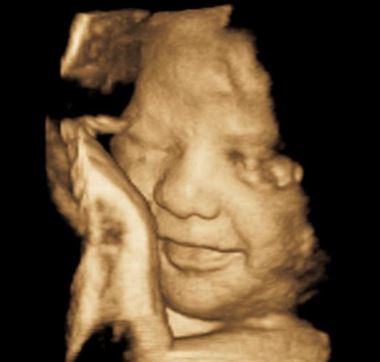

Είναι υπερηχογράφημα που αποσκοπεί στην ανίχνευση τυχόν προβλημάτων της ανάπτυξης και της ανατομίας του εμβρύου. Όλα τα όργανα πλέον έχουν αναπτυχθεί και ο προγενετιστής εξετάζει ένα-ένα τα συστήματα του εμβρύου, προσδιορίζει το φύλο του, τον αριθμό των αγγείων και την έκφυση του ομφαλίου, τη θέση και μορφή του πλακούντα, το μήκος του τραχήλου της μήτρας και τη ροή του αίματος που αρδεύει τη μήτρα. Ακόμη, επαναπροσδιορίζεται ο κίνδυνος για σύνδρομα όπως Down, εκτιμάται η πιθανότητα ανάπτυξης υπερτασικών διαταραχών της κύησης και η πιθανότητα πρόωρης έναρξης τοκετού.